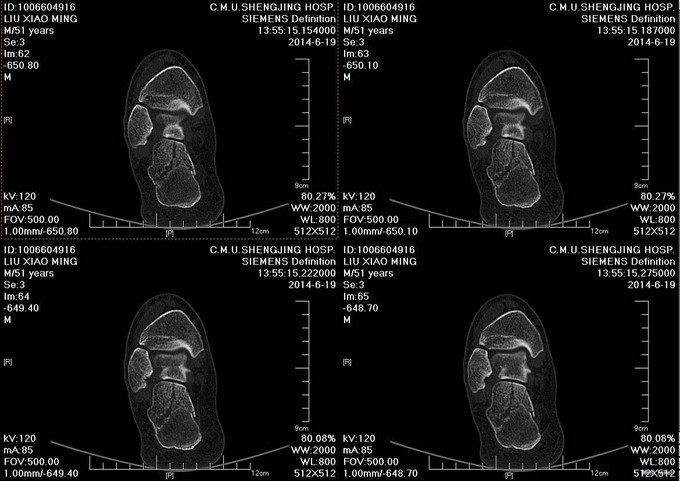

患者及其家属自述于2014-8-27 13:30 因在自家干活时不慎从2米高梯子上摔下,当时患者意识清醒,无法站立,左踝部疼痛、肿胀、活动受限;被急送往中国医科大学附属盛京医院,经急诊医师会诊后,建议住院治疗,患者及其家属今为进一步治疗,要求入院,我科以“右跟骨骨折”为诊断收入我科;患者伤来无发热、无头晕、恶心呕吐,无呼吸困难,既往饮食睡眠可,大小便正常;

右踝关节可见肿胀,足跟部压痛(+),未触及骨擦音及骨擦感,足部感觉正常,踝关节及足趾活动正常,足背动脉搏动可触及。

患者入院后完善检查,给予患肢抬高位,给予冷疗、抗炎、消肿等对症治疗后。约10天后足踝部褶皱试验(+) 。 查无手术禁忌症后行右跟骨骨折切开复位内固定术。术后继续给予冷疗,消肿,抗炎等对症治疗。3周后拆线治疗后出院。